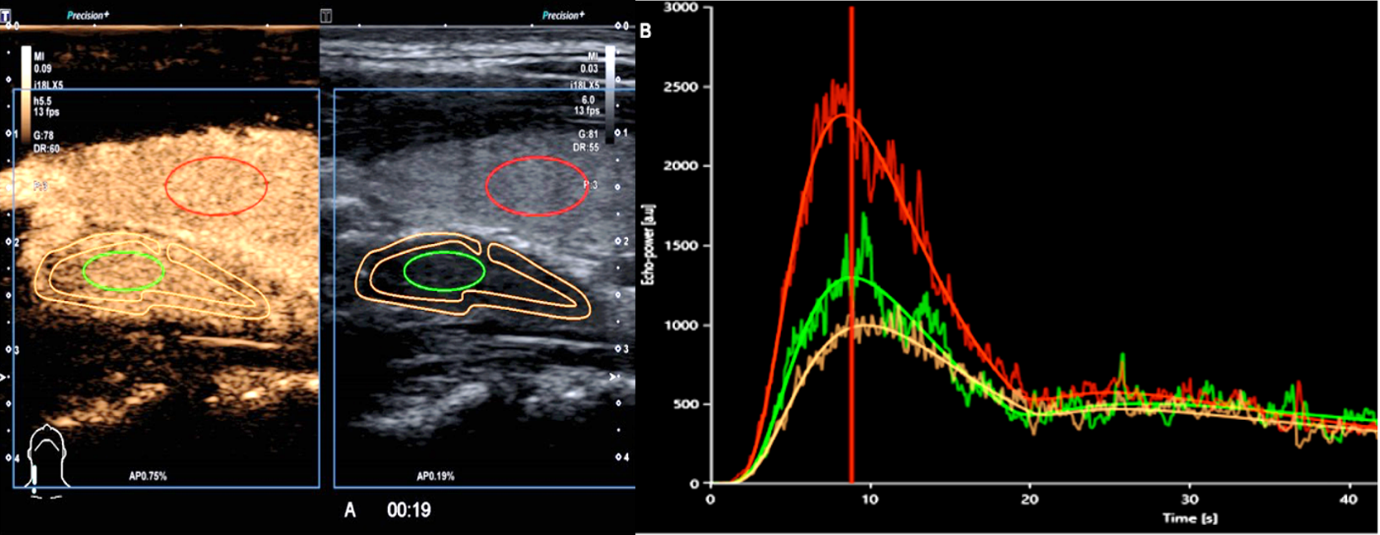

Latvijas zinātnieki ir izpētījuši šo jauno diagnostikas metožu iespējas EĶ veidojumu raksturošanā, izmantojot audu blīvuma mērīšanu (elastogrāfija) un kontrasta ultrasonogrāfija (CEUS) –

pacientam caur venozo katetru ievada kontrastvielu, ar ultrasonogrāfiju pēta kontrastvielas krāšanos un izskalošanos no epitēlijķermenīšiem, lai varētu raksturot veidojuma tipu.

Kontrasta ultrasonogrāfijas izmeklējums epitēlijķermenīša adenomai